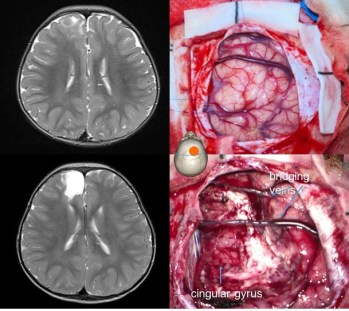

la résection est guidée par l’anatomie, la neuronavigation, et parfois des modifications de la voûte (soufflure) ou du cortex (coloration, déplissement, induration).

chaque fois que possible, la chirurgie est sulcale, ouvrant le sillon bordant la tumeur et respectant les vaisseaux à destinée du gyrus adjacent. lorsque le plan pial se sépare bien de la lésion (en particulier dans les dysplasies), la dissection sous-piale permet au mieux de respecter le gyrus adjacent.

la dissection vasculaire minutieuse permet également de respecter les vaisseaux qui traversent la tumeur.